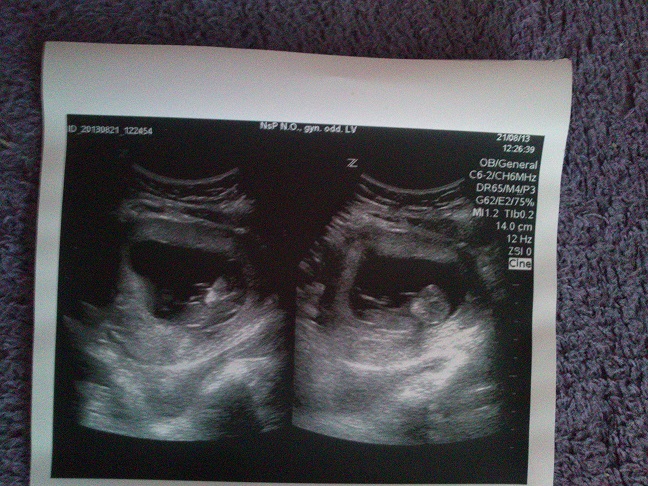

baby poradte mi .som 33t.t .brusko my zevraj kleslo dole kazdy mi to vravi a mne sa aj tak ulavilo ze samy lepsie dycha ale strastne ma picha odspodu .pri malom som nic take nemala .mala sa hybe pohyby citim pekne mozu to byt uz poslickovia nie je nato nejak skoro .termin mam 11.marca maleho som mala cisarskym

nasa malickaMiška ma 1800g a budem rodit znova cisarskym

budeme mat dievcatko na 100percent